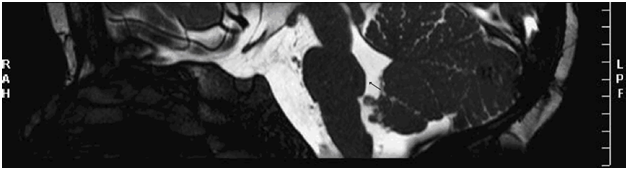

The temporal bones Computed Tomography (CT scan) and 1,5 Tesla Magnetic Resonance Imaging (RMI), performed after functional diagnosis, showed several anatomical malformations (Figure 1). The CT scan showed bilateral internal auditory canal stenosis; the axial and coronal measures of the canals were 1millimeter for both sides. The MRI showed an absence of cochlear and vestibular nerve on the right side, and of the cochlear portion on the left side. Additional analyses were performed to further investigate the anatomical/medical status prior to implant. Neuro-radiological imaging using a 3 Tesla MRI, to provide finer details of cerebral and neural structures, confirmed cochlear-vestibular nerve malformations, and evidenced finer detail of the anatomical deviations previously observed: brain stem malformation, flattening of the ventral pons and a median posterior "pontine cap". A horizontal pontine cleft was evidenced in the posterior pons. The bulbopontine junction was poorly defined, and a thinning of the ponsmesencephalic junction was observed. The median cerebellar peduncles appeared shorter and thinner than normal size.

Figure 1 CT scans: normal inner ear and stenotic internal auditory canal.

The inner ear structures were normal on both sides. Hypoplasia of the internal auditory canals bilaterally was observed. Bilateral cochlea-vestibular nerves were not entirely recognizable. The facial nerve was visible on both sides, but the entry point was forward and anterior to the internal auditory canal. In normal condition the facial nerve and the nervus intermedius leave the brainstem near the dorsal pons at the pontomedullary junction (the cisternal segment of the facial nerve). Within the cerebellopontine angle (CPA), the nerve travels anterolaterally into the porus acousticus of the internal auditory canal (IAC), anterior to the vestibulocochlear nerve.9 In cases of severe malformations it’s better to perform a stronger MRI to define anatomical details and to obtain indications useful for the treatment.